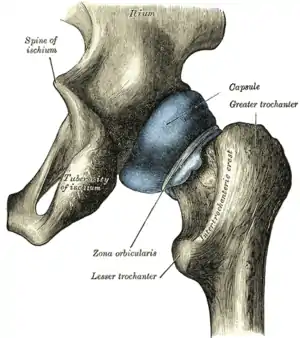

![]() Vedere posterioară a capuslei (destinse) a articulației coxofemurale. Osul iliac se vede în partea de sus a imaginii. | |